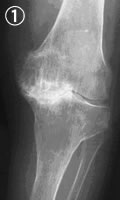

![]() |

| 白いところが石灰化した部分 |

血液検査では、炎症を示すCRPの値が6+に(正常値0)。X線では、両膝の関節軟骨、半月板、腱などが石灰化し、硬くなっていることがわかりました(写真1)。関節穿刺で関節液を調べたところ、偽痛風の特徴である、ピロリン酸カルシウムの結晶が認められました(写真2)。偽痛風は痛風と同じような症状を起こしますが、尿酸値は正常範囲内です。